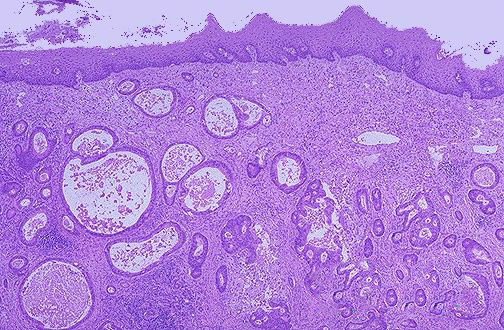

病理上把白塞病肠溃疡分为坏死型、肉芽肿型以及混合型。坏死型为急性、亚急性病变,肉芽肿型为慢性病变,混合型介于二者之间。镜下可见肠黏膜水肿,黏膜固有层和黏膜下组织内的肠淋巴管扩张。肠的血管病变为伴随溃疡出现的血管炎性变化,主要表现为血管内膜的肥厚。以黏膜下组织的血管,特别是静脉为明显。这种血管的病变与溃疡的大小无关,受时间推移的影响,急性期溃疡(坏死型)的血管病变比慢性期溃疡(肉芽肿型)血管炎性病变为轻。溃疡越深,血管病变越明显。而无溃疡的肠黏膜,多见不到明显血管炎性变化。这种血管病变与肺结核、克罗恩病、溃疡性结肠炎的血管病变基本上无太大差异。